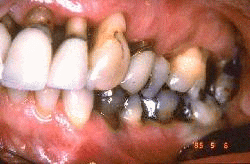

Esta imagen demuestra la condición después de 10 años. Las coronas anteriores se han rehecho. El paciente tiene una línea de la sonrisa baja y las líneas de preparación supragingival no perturban su estética. Ella ha mantenido un excelente control de placa bacteriana y no se obseva signos de enfermedad periodontal. La abrasión ocasionada por el cepillado dental ha aumentado. Ella acostumbra usar un cepillo suave y pasta dental no abrasiva para reducir el desgaste dental por el cepillado diario.